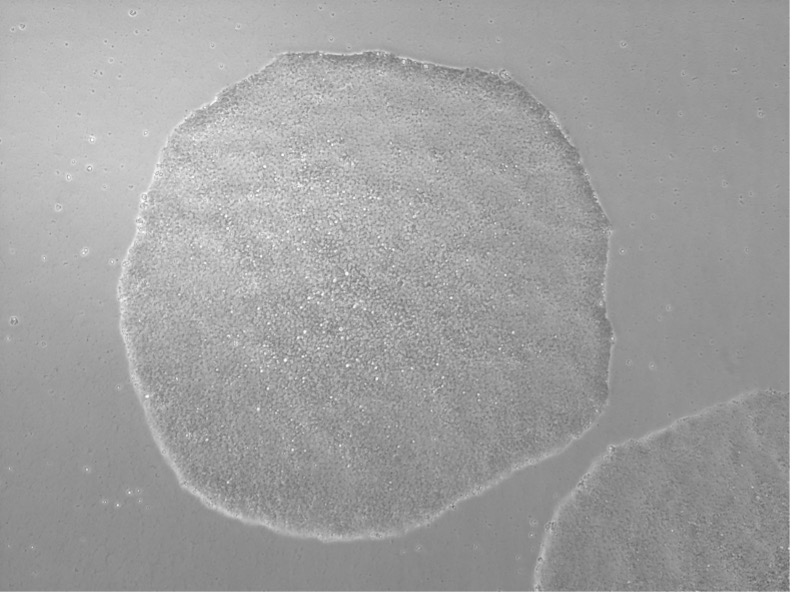

| 1、细胞系形态学鉴定:普通光学显微镜,低倍镜,1张 | 2、AP染色:普通光学显微镜,低倍镜,1张 |